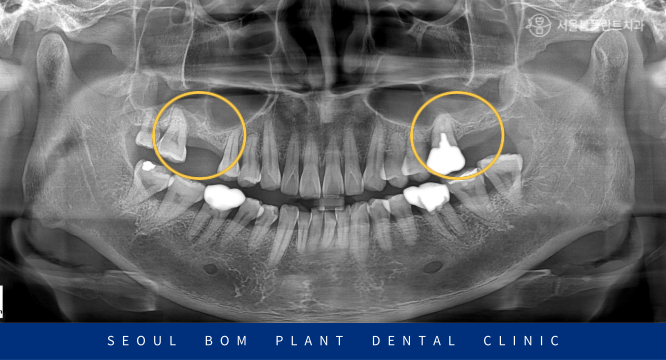

50대 남성분으로 오륜동치과 내원 시

위턱 양측 어금니 상실로 인해

힘들어하고 계셨습니다.

상실된 부위 외에도

위턱 오른쪽 두 번째 큰 어금니(#17)와

왼쪽 첫 번째 큰 어금니(#26)도

치아 주변으로 잇몸뼈가 많이 약해져

동요도가 있었답니다.

그런데 환자분의 경우

남아 있는 뼈의 양이 적고,

상악동이 많이 내려와 있는

상황이었습니다.